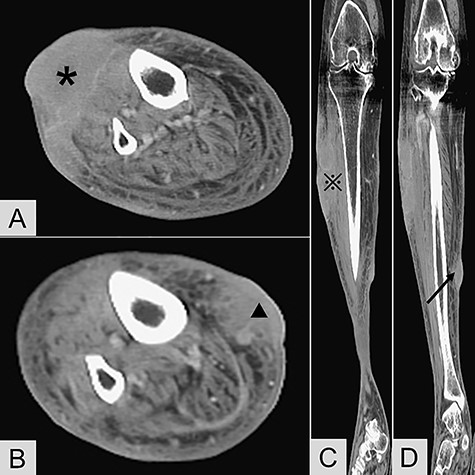

Contrast-enhanced computed tomography revealed (A) transverse view of the anterior lesion of right lower leg (*); (B) transverse view of the medial lesion of right lower leg (▲); (C) coronary view of the anterior lesion (

); (D) coronary view of the medial lesion (black arrow).

Physical examination revealed two red and violaceous skin lesions over the right lower leg, ~9 and 3 cm in size, respectively. The lesions were erythematous, had ill-defined borders and were tender on palpation. Local heat and swelling of the skin around the lesions were also noted. Laboratory data, including a complete blood count and biochemical studies, revealed no significant findings. Contrast-enhanced computed tomography of the lower limbs revealed an abnormal space-occupying lesion about 9 cm × 7.5 cm × 3.3 cm in size, at the anterior aspect of the right lower leg. It showed heterogeneous density, heterogeneous contrast enhancement, and involvement of the subcutaneous area, superficial fascial planes and muscle layer. Another small non-specific lesion about 3 cm in size was located at the medial aspect of the right lower leg, with similar radiological features (Fig. 1). With a provisional diagnosis of skin tumors with associated cellulitis of the right lower leg, she was subsequently admitted to our institution for further investigations and antibiotic treatment.